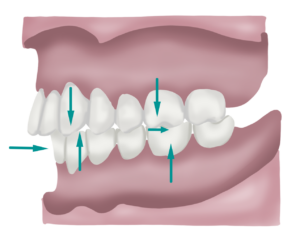

Classe II Molar

La classe II molar es dona quan la mandíbula està excessivament retruïda respecte el maxil·lar. Avaluem els mil·límetres de retrusió agafant com a referència la posició dels primers molars definitius .

Una mandíbula excessivament retruïda pot provocar problemes funcionals ja que tindrem una compressió dels teixits tous de l’articulació temporo mandibular i també tindrem una excessiva tensió a nivell muscular ja que no és una posició còmoda per mastegar i exigeix un esforç extra al cos. Sovint trobem també una sèrie d’alteracions posturals associades, el que anomenem síndrome de disfunció postural descendent, en el qual es poden invertir les curvatures vertebrals en els casos més accentuats.

A part d’aquest problema funcional, la classe II també sol suposar un problema estètic per l’individuja que les dents inferiors queden molt en segon pla i el mentó molt enrere respecte les dents de dalt.